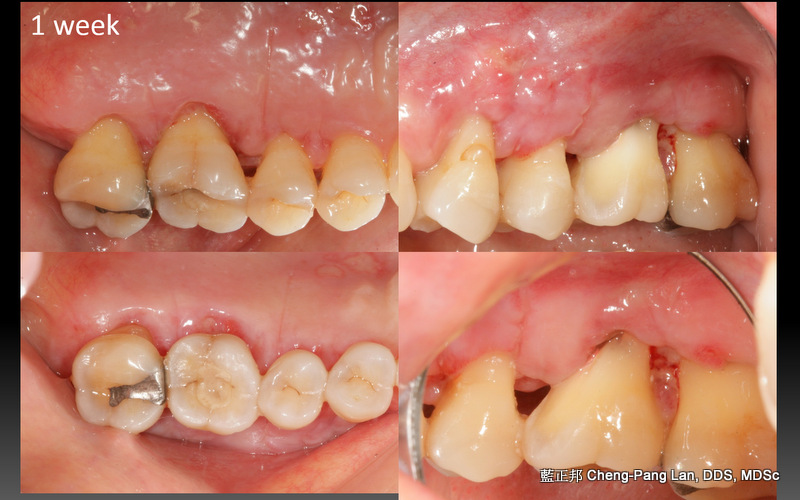

拔牙或植牙?

老師常常暗示著大家,implant與natural teeth之間,留下natural teeth比較好。這個我真的相信,在牙周病科的每一位學弟妹也都相信,甚至我相信週六在場的牙周病醫師都認同,但是大家有沒有想過,每隔週三一起開會的Prosthodontist、 Orthodontist都相信嗎?甚至,從實習醫師畢業就進入職場服務病人的學弟妹們,都相信嗎?